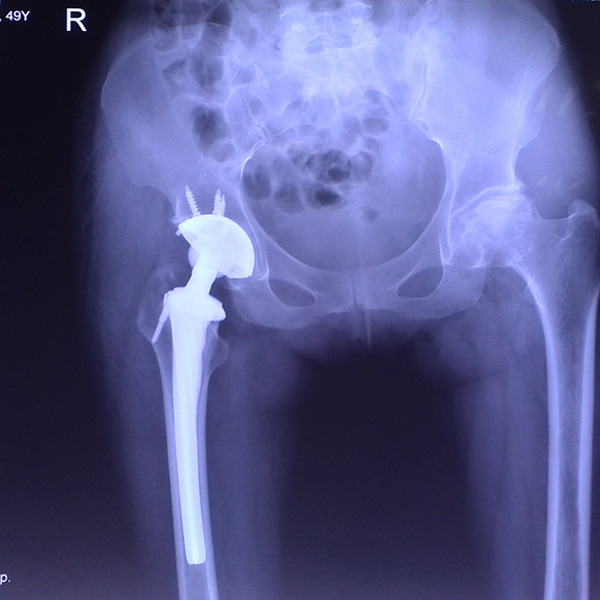

• 髖關節翻修髖關節翻修手術后手術前

髖關節翻修

患者蘇某,女性,11年前因“左髖關節屈曲攣縮畸形”行左側人工全髖關節置換,近來感覺左髖關節疼痛,不敢行走,經“攜生醫療平臺”就診于哈......

• 右側全髖關節置換右側全髖關節置換手術后手術前

右側全髖關節置換

患者姜某某,女50歲,診斷為“股骨頭壞死”,右側髖關節疼痛到不能生活自理。經平臺推薦到哈爾濱醫科大學附屬第二醫院骨關節科就診,患者想......